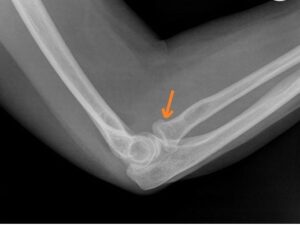

[toggle title=”Ön ve Arka Yağ Yastıkçığı Bulgusu” state=”close”]

Normalde eklem kapsülünde yağ yastıkçıkları bulunur.

Anterior yağ yastıkçığı koronoid fossada bulunur ve normal grafide de ince bir çizgi halinde görülebilir. Ancak anterior yağ yastıkçığı ayrışmış ve daha belirginleşmişse buna Yelken Bulgusu (Sail sign) denir ve görülmesi patolojiktir.

Olekranon fossada bulunan posterior yağ yastıkçığının grafide görülmesi ise her zaman patolojiktir.

Bazı non-deplase kırıklarda kırık hattı görülemeyebilir ve anormal yağ yastıkçığı işareti yaralanmanın tek bulgusu olabilir.

Travma öyküsü olan hastalarda yağ yastıkçığı görülmesi aksi kanıtlanana kadar kırığa sekonder düşünülmelidir.